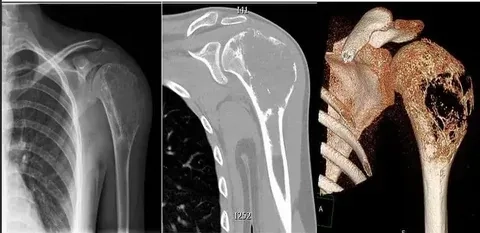

• Diagnosis involves imaging tests and a biopsy, which also helps determine the sarcoma stages and informs the most effective treatment plan for the patient.

Image of a soft tissue sarcoma